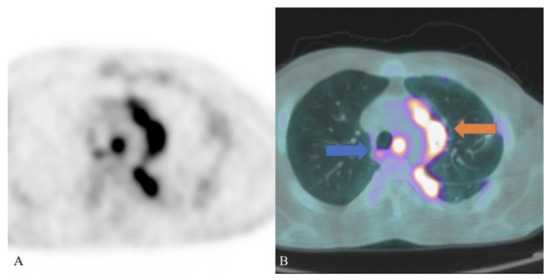

- Daghigh, A.; Grüner, J.M.; Mørup, P. Intestinal FDG-PET/CT imaging of an Eritrean with schistosomiasis seen in Denmark. Eur. J. Hybrid. Imaging 2019, 3, 17. [Google Scholar] [CrossRef] [PubMed]